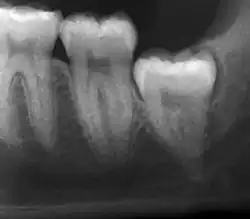

| Diagnostic method | Examination, x-ray |

Impacted wisdom teeth are classified by their direction of impaction, their depth compared to the biting surface of adjacent teeth and the amount of the tooth's crown that extends through gum tissue or bone. Impacted wisdom teeth can also be classified by the presence or absence of symptoms and disease. Screening for the presence of wisdom teeth often begins in late adolescence when a partially developed tooth may become impacted. Screening commonly includes a clinical examination as well as x-rays such as panoramic radiographs.

If the tooth cannot be assessed with clinical exam alone, the diagnosis is made using either a panoramic radiograph or cone-beam CT. Where unerupted wisdom teeth still have eruption potential several predictors are used to determine the chance of the teeth becoming impacted. The ratio of space between the tooth crown length and the amount of space available, the angle of the teeth compared to the other teeth are the two most commonly used predictors, with the space ratio being the most accurate. Despite the capacity for movement into early adulthood, the likelihood that the tooth will become impacted can be predicted when the ratio of space available to the length of the crown of the tooth is under 1.[6]: 141